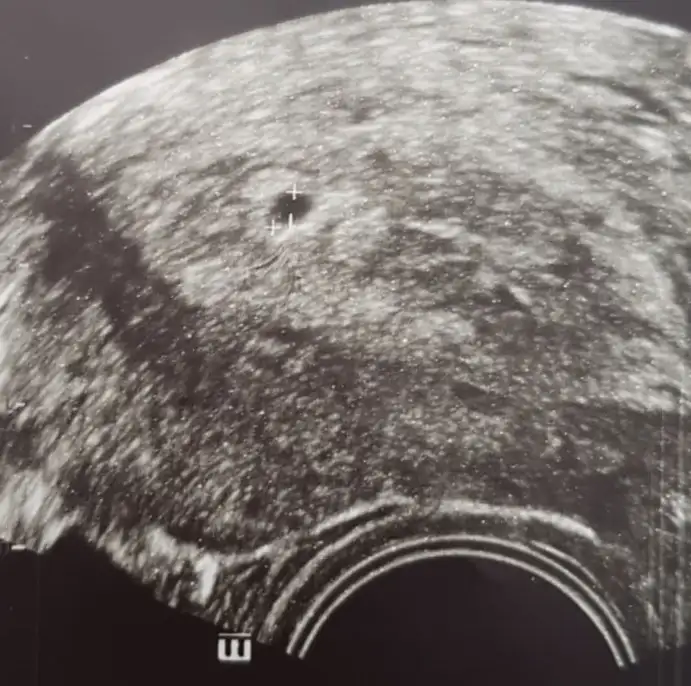

Kızlar merhaba bugün ilk defa kese gördük beta 2904, doktorlar kese mi değil mi bilemedi çok değişik süreçlerden geçtiğim için , 16 aralıkta transfer oldum daha yeni kese görüldü beta bi ara düştü hafif yükseldi ilaçları bıraktım adet olmayı beklerken değerlerim yükseldi sonuçta bu durumdayız

Bu tarihte beta hcgnin daha yüksek olması gerekirdi diye biliyorum ....